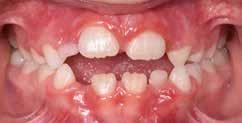

Presentazione del caso > F.V, bambino di cinque anni, presenta una malocclusione di II Classe scheletrica, III Classe dentale molare e canina destra e sinistra, morso inverso anteriore. Le arcate dentali mostrano usura degli elementi dentari anteriori a causa dell’occlusione patologica. Le linee mediane, superiore ed inferiore, sono centrate; il frenulo labiale superiore patologico per un’eccessiva estensione inter-incisale.

Dall’esame clinico si evince la III Classe dentale, l’inversione anteriore e l’over-jet negativo.